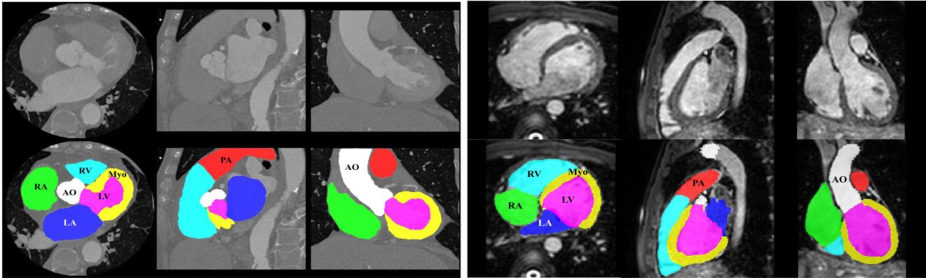

Currently, the Whole Heart Segmentation (WHS) is an imperative preliminary action for a wide range of clinical treatments. For example, the pathology localization and accurate ventricular dimensions [13, 14], which aims to delineate seven different heart substructures, as outlined in Table I, from the whole cardiac images (see in Fig. 1).

The precise heart quantification requires the subtle segregation of different heart substructures. For instance, the ejection portion and the myocardial mass are estimated from the segmented ventricular and the myocardial results, respectively, which are critical pointers of cardiac disorder detection. The whole heart’s manual delineation is labor-intensive and tedious, necessitating almost eight hours for an individual subject [15]. Consequently, the designing of computer-aided methods to investigate medical images automatically are highly demanding. However, an automated segmenting of a whole heart is also challenging due to the cardiac anatomical shape variations and the indefinite borders among different heart substructures [1], as depicted in Fig. 1. Achieving entirely computerized WHS is arduous due to the following hurdles:

All the comprehensive experiments were conducted utilizing publicly available MM-WHS- dataset [1], as it is commonly used in recent articles (see in Table II), which contains cardiac whole heart volumetric MRI and CT data. The VOIs include the seven different substructures in the utilized WHS dataset, as described earlier in subsection I-A (see in Table I). The different substructures, such as LV, RV, LA, RA, Myo, AO, and PA (see in Fig. 1) of both the CT and MRI are labeled as , , , , , , and , respectively. We aim to segment those seven organs from both the cardiac CT and MRI scans. Hence, we have termed it a multi-class (8-classes) segmentation task, including the background and seven different heart substructures. All the experimental WHS approaches are assessed following a leave-one-out evaluation strategy [37].